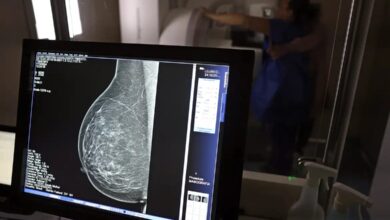

O câncer de mama, tradicionalmente mais comum em mulheres acima dos 50 anos, tem apresentado crescimento preocupante entre mulheres com menos de 40. Pesquisas recentes indicam que os casos nesse grupo costumam ser diagnosticados em estágios mais avançados, o que dificulta o tratamento e compromete o prognóstico. Por isso, a prevenção e o diagnóstico precoce tornam-se ainda mais importantes.

Em resposta a esse cenário, o Ministério da Saúde anunciou recentemente que vai garantir o acesso à mamografia no SUS a mulheres entre 40 e 49 anos, mesmo que não apresentem sinais ou sintomas da doença, com o objetivo de antecipar o diagnóstico e tratamento.

Além disso, a mudança de comportamento deve se basear, principalmente, em manter os exames de rotina em dia. “A partir dos 40 anos de idade, todas as mulheres devem realizar a mamografia de rastreamento anual e prestar atenção no próprio corpo. Ao identificar algum nódulo ou alteração na mama, é preciso buscar avaliação médica especializada”, reforça Aline. Segundo ela, cuidados com a alimentação, a prática de atividade física e evitar, além do tabagismo, o uso indiscriminado de hormônios são primordiais para reduzir o risco de desenvolver a doença.